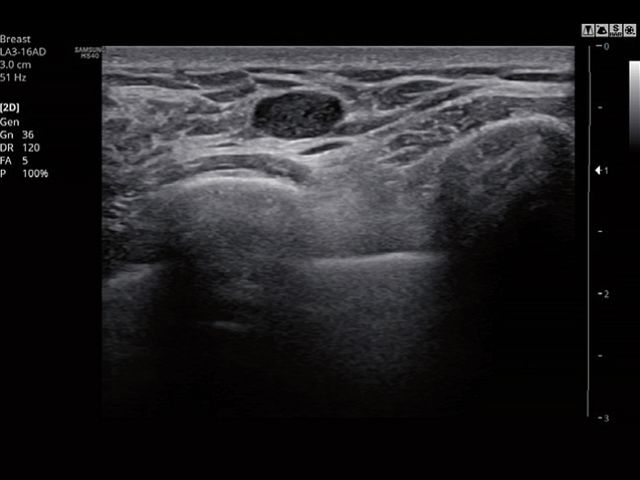

The feature, which analyzes selected lesions in the breast ultrasound study and shows the analysis data, applies BI-RADS ATLAS* (Breast Imaging-Reporting and Data System, Atlas) to provide standardized reporting; and helps diagnosis with the streamlined workflow.

* It is a registered trademark of ACR and all rights reserved by ACR.